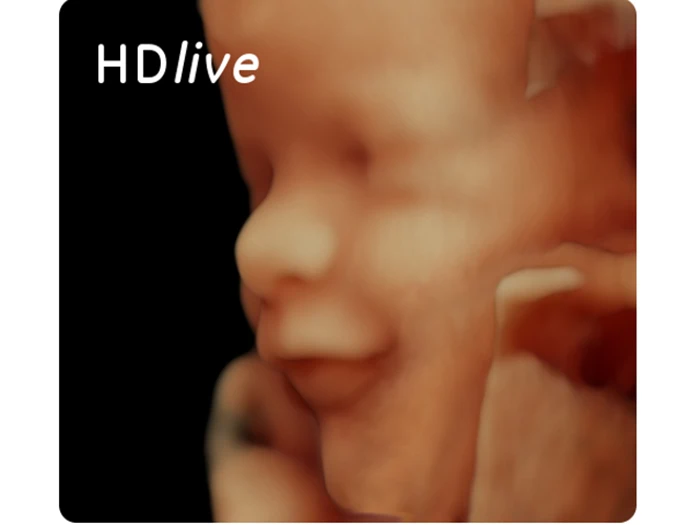

Ved 3D/4D scanning fornemmes den tredje dimension - dybde. Dette gør, at du oplever at få billeder, der i langt højere grad svarer til at se dit barn i virkeligheden end ved de almindelige 2D scanninger. Ved en scanning i 3D kan man virkelig få et indtryk af, hvordan ens barn ser ud med fine detaljer og personlige træk. Den fjerde dimension betyder, at der er bevægelser med, altså at du ser dit barn "live" i 3D. Ligger barnet i en god position for, at vi kan se ansigtet, vil det være muligt at se, hvis barnet fx smiler, smasker, gaber eller sutter på sine fingre.

3D/4D scanning er blevet utrolig populær, og vi kan med højt uddannet og trænet personale, samt scanningsudstyr med nyeste teknologi, præstere billeder og sekvenser i topklasse.

Herefter går vi over i 3D/4D scanning, hvor vi finder de helt rigtige scanningsvinkler for at kunne frembringe de helt optimale billeder og sekvenser.